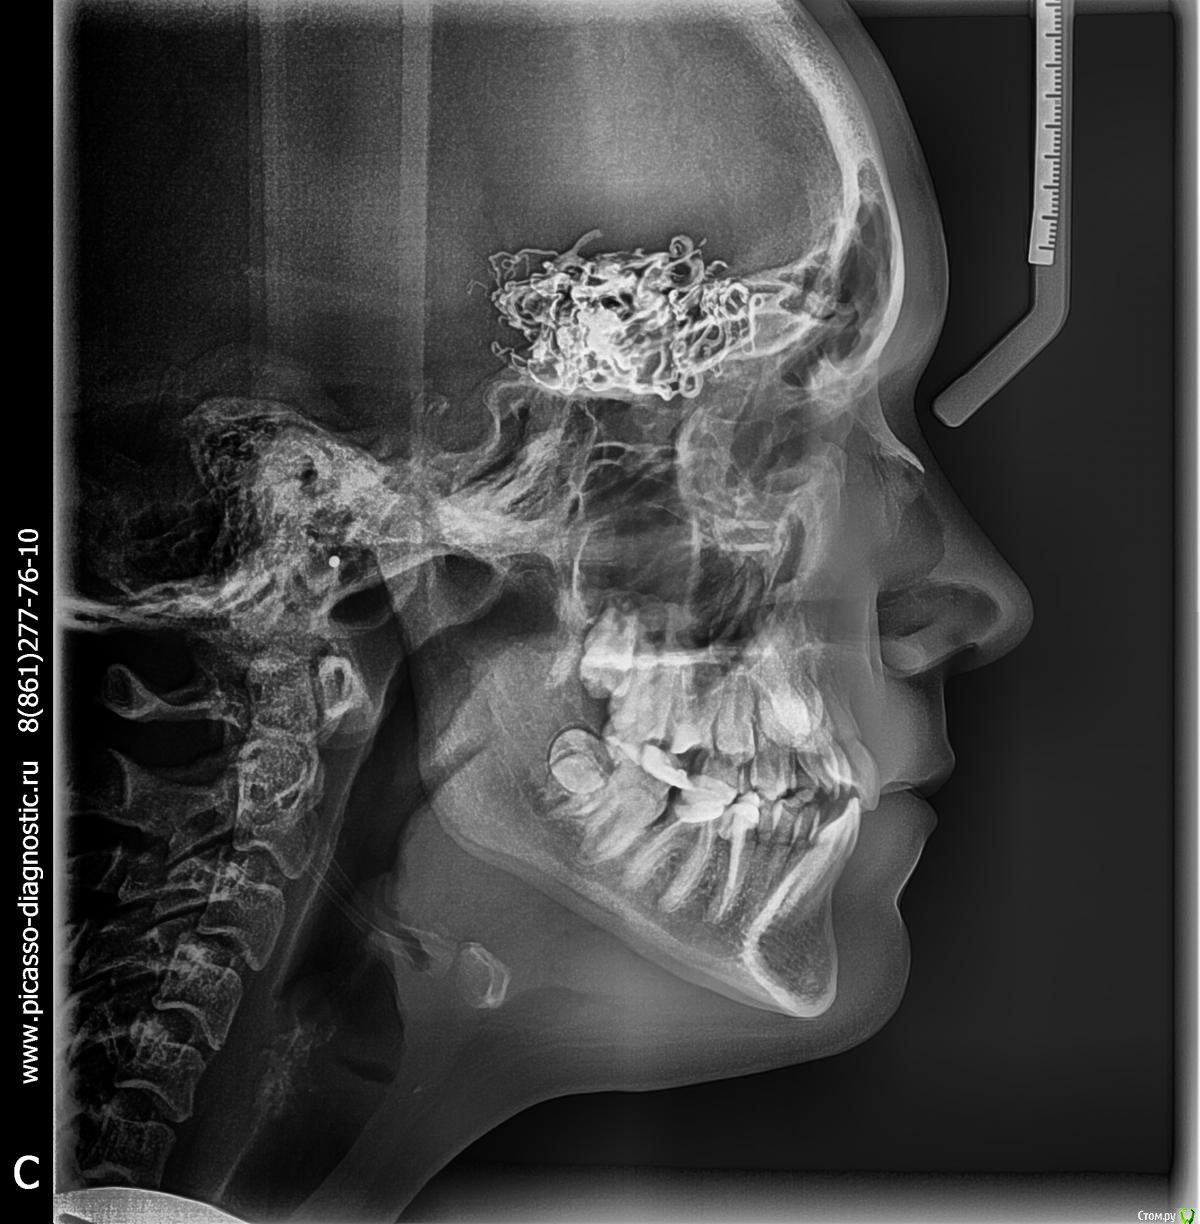

vov4ikdent Опубликовано 30 января, 2018 Поделиться Опубликовано 30 января, 2018 Коллеги, случайная находка на ТРГ. Что это? Никогда такого не видел. Ссылка на комментарий

kramer Опубликовано 30 января, 2018 Поделиться Опубликовано 30 января, 2018 Жалоб не было, сел расчет делать и увидел. Кт надо же как-то обосновать, что сказать родителям. Пациентка девочка 14 лет. Назначена на пятницу. Думаю, куда на консультацию направить.Ну явно какая-то сосудистая мальформация. Радиоплотность должна говорить о кальцификации. имхо 2 Ссылка на комментарий

kramer Опубликовано 30 января, 2018 Поделиться Опубликовано 30 января, 2018 (изменено) Показал знакомому нейрохирургу, он предположил краниофарингиому. Девочке нужна консультация нейрохирурга и обследование Изменено 30 января, 2018 пользователем kramer 2 Ссылка на комментарий